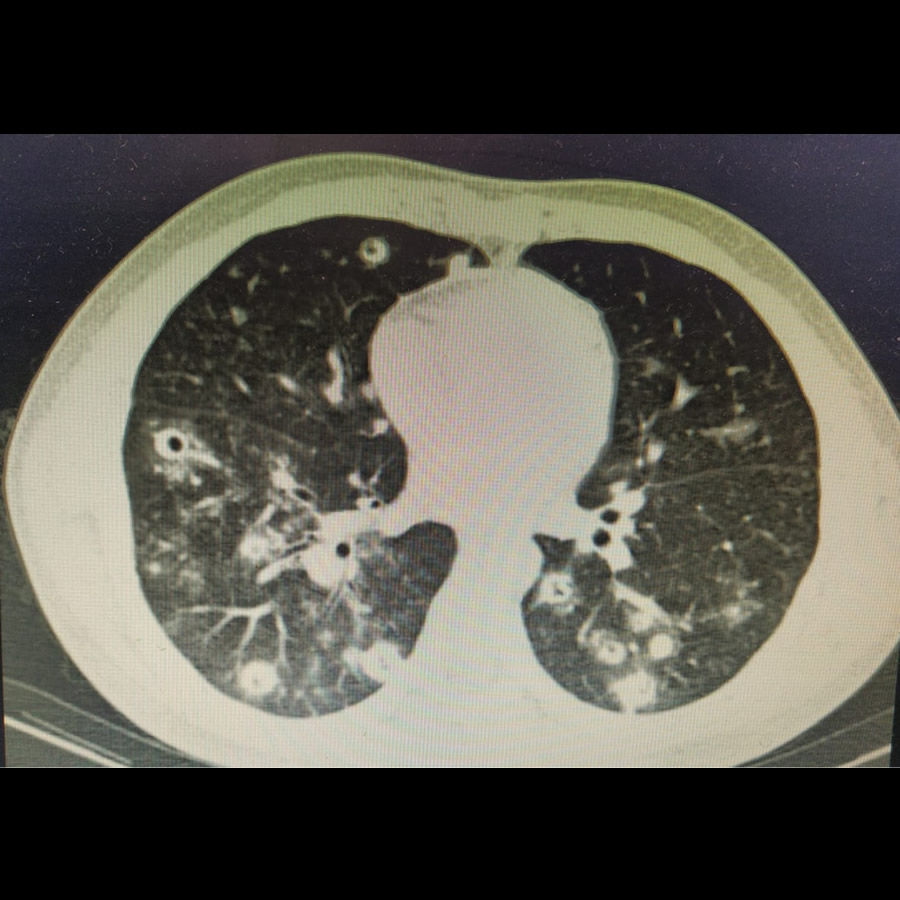

Mayo 2023. Instituto Roentgen Paciente masculino de 21 años, oriundo de Corrientes Trabajador en tambo APP: covid + 12/2022 alta epidemiológica. No vacunado APT: Tabaquista 11 paq/a MC: disnea + fiebre persistente